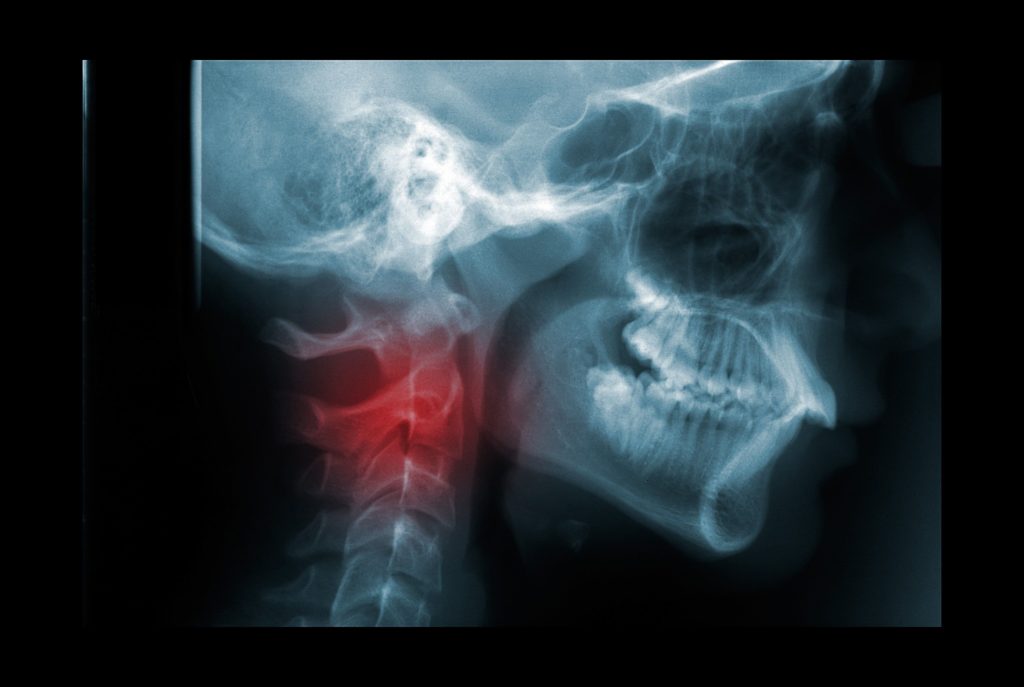

WebEl latigazo cervical produce contracturas, rectificación o incluso lesiones más graves, como protrusiones o hernias. Para obtener una indemnización por cervicalgia justa, la. WebEl nuevo baremo de accidentes de tráfico ha puesto en el ojo del huracán los que denomina como «traumatismos menores de la columna cervical». La idea que subyace es que.

WebEn el presente supuesto se reclama una indemnización por accidente de tráfico al entender que una secuela de esguince cervical que ha sido valorada en 3. WebLesiones en cabeza, cuello y cara: esguince cervical, fracturas, abrasiones faciales y hematomas de gran importancia. Lesiones en extremidades: traumatismos,. WebEs importante aclarar que para poder pedir después una indemnización por cervicalgia postraumática tras un accidente de trafico hay que acudir al médico para que dictamine. WebPara formalizar una reclamación por lesión cervical, los afectados disponen de tres vías de actuación: presentar una denuncia contra el culpable del siniestro (la vía. WebLos síntomas más representativos de un latigazo cervical son dolor de cuello irradiado a hombros y brazos, dolor de espalda, mareos, vómitos,. WebEs recomendable recibir el tratamiento del latigazo cervical y las pautas a seguir por un profesional fisioterapeuta. En Indemnización por Accidente, le podemos recomendar. WebLo primero que debemos hacer tras sufrir un accidente de trafico es acudir al hospital, donde nos harán las pruebas y revisiones necesarias para realizar un buen diagnóstico.